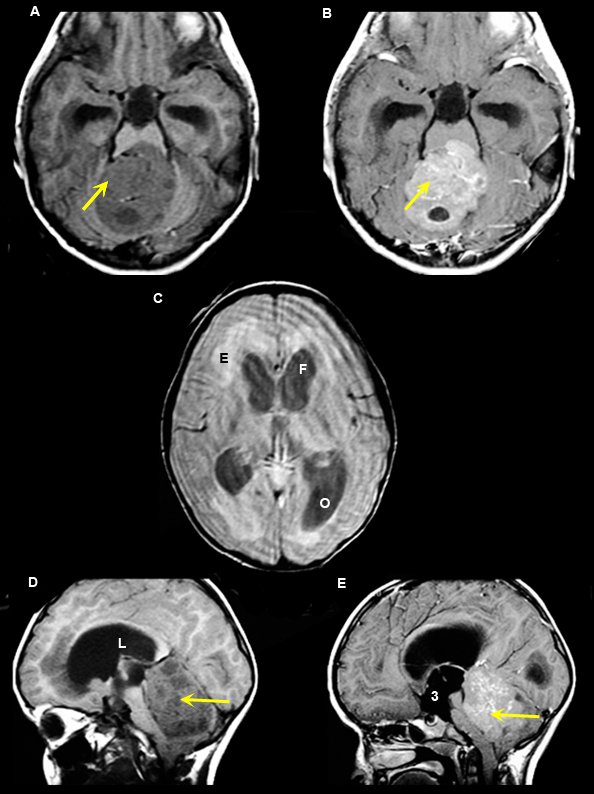

Figure 3

A. Pre-contrast axial T1 wtd. MRI

B.

Post-contrast axial T1 wtd. MRI

C.

Axial T2 wtd. MRI

D.

Pre-contrast sagittal T1 wtd. MRI

E.

Post-contrast sagittal T1 wtd. MRI

Case 3:

10 year old boy with papilledema resulting from obstructive hydrocephalus.

Imaging findings: Figure 3

- Intensely enhancing tumor (yellow arrows in figs B, E) is seen involving the roof of fourth ventricle, particularly involving the adjacent vermis.

- Obstructive hydrocephalus from medulloblastoma is noted with marked enlargement of lateral ventricles [frontal horns (F in fig. C), occipital horns (O in fi.g C), lateral ventricle (L in fig. D) and third ventricle (3 in fig. E)].

- Figs. A, D: Pre-contrast MR images show non-specific mass with hydrocephalus.

- Figs. B, E: Post-contrast MR images demonstrate enhancing characteristics of the tumor along the roof of fourth ventricle (arrows).

- Fig. C: T2 wtd. flair image demonstrates hydrocephalus involving the lateral ventricles resulting in periventricular edema (E in fig. C).

Final impression:

Medulloblastoma

Medulloblastoma is a malignant primary brain tumor originating from the roof of fourth ventricle. Most common in children and young adults. Tumor, because of its location, compresses the fourth ventricle and causes hydrocephalus. Symptoms are primarily secondary to increased intracranial pressure from hydrocephalus.